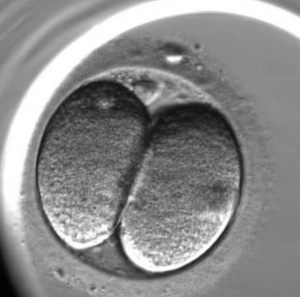

L’enregistrement du développement de l’embryon est le suivant :

Pour l’évaluation de la qualité des embryons on utilise la méthode d’analyse morphologique. Les embryons sont évalués selon les critères suivants : la quantité des blastomères, l’égalité des blastomères et la présence de fragmentation (des blastomères normaux qui ont été détruits). Cependant, cette méthode qui est la plus ancienne a ses inconvénients, elle est subjective (elle dépend de l’expérience et du niveau de l’embryologiste), un embryon est extrêmement variable durant son développement un embryon de mauvaise qualité de deux jours peut se transformer en un bel enfant en bonne santé. En ce moment, on utilise une nouvelle méthode d’évaluation de la qualité des embryons c’est l’embryoscopie. Son principe est le suivant : toutes les 10 ou 20 minutes on prend une photo de l’embryon en 7 couches, avec l’utilisation d’un programme informatique, on applique les images l’une sur l’autre pour en faire une video, c’est « le résumé » de chaque embryon. Avec l’utilisation d’un programme informatique spécifique, on mesure les paramètres clés du développement embryonnaire :

Le moment de la première division ;

Le commencement de la deuxième division (l’apparition du troisième blastomère)

La fin de la deuxième division (l’apparition du quatrième blastomère)